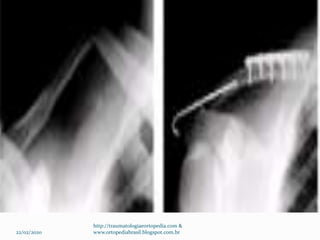

Técnica cirúrgica – Grupo II tipo II

Incisão Fita de Dacron de 3mm

Parafuso de estabilização

coroclavicular com arruela

Sutura Tevdek no. 5 sob a

arruela como banda de tensão